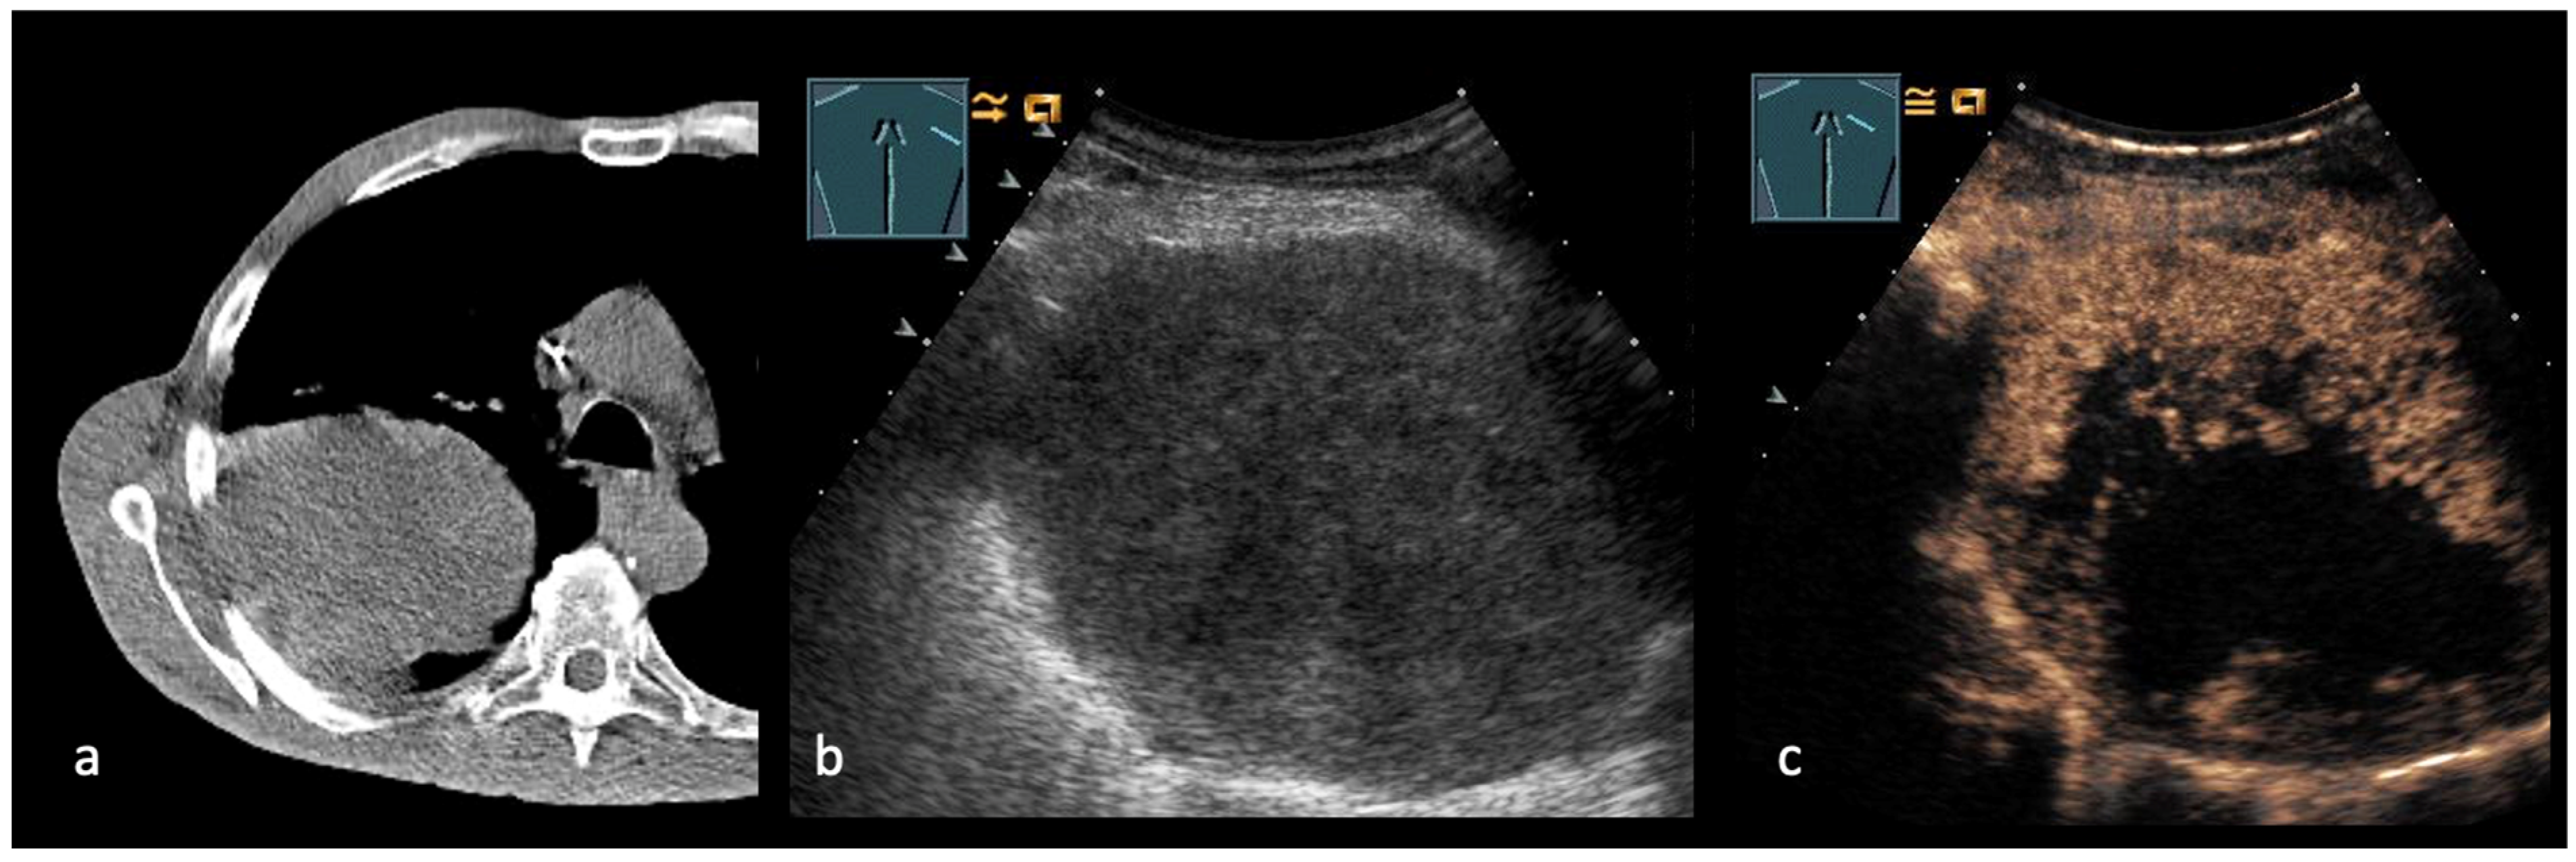

3. Transthoracic Ultrasound in the Evaluation and Characterizing of Local Tumor Size (T-Stage)

- Safai Zadeh, E.; Huber, K.P.; Görg, C.; Prosch, H.; Findeisen, H. The Value of Contrast-Enhanced Ultrasound (CEUS) in the Evaluation of Central Lung Cancer with Obstructive Atelectasis. Diagnostics 2024, 14, 1051. [Google Scholar] [CrossRef]

- López González, F.J.; García Alfonso, L.; Cascón Hernández, J.; Ariza Prota, M.; Herrero Huertas, J.; Hermida Valverde, T.; Ruíz Álvarez, I.; Torres Rivas, H.E.; Fernández Fernández, L.M.; Enríquez Rodríguez, A.I.; et al. Biopsy of Intrapulmonary Lesions in Lungs with Atelectasis and Pleural Effusion. Arch. Bronconeumol. 2021, 57, 438–439. [Google Scholar] [CrossRef]

- Lei, Z.; Lou, J.; Bao, L.; Lv, Z. Contrast-enhanced ultrasound for needle biopsy of central lung cancer with atelectasis. J. Med. Ultrason 2018, 45, 461–467. [Google Scholar] [CrossRef] [PubMed]